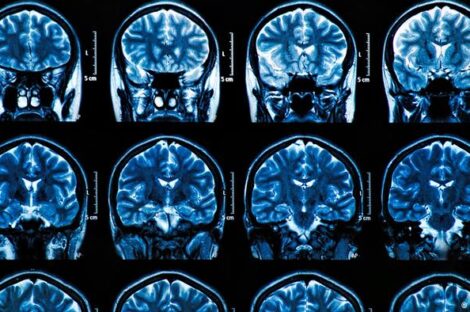

علماء يتمكنون من اختبار لقاح على 33 مريضاً من مركز اتحاد السرطان الألماني DKTK، يستهدف نوعاً من أورام الدماغ، وأشارت…